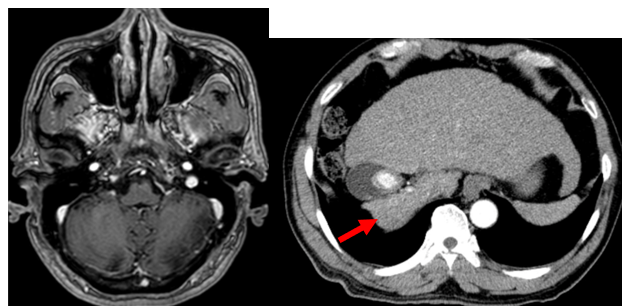

Hình 3: Hình ảnh cộng hưởng từ sọ (bên trái) và cắt lớp vi tính ổ bụng (bên phải) tháng 9/2022: Chưa phát hiện hình ảnh tổn thương (hình bên trái). Hình ảnh u gan phải sau điều trị kích thước 17x13mm, không tăng sinh mạch (mũi tên đỏ).